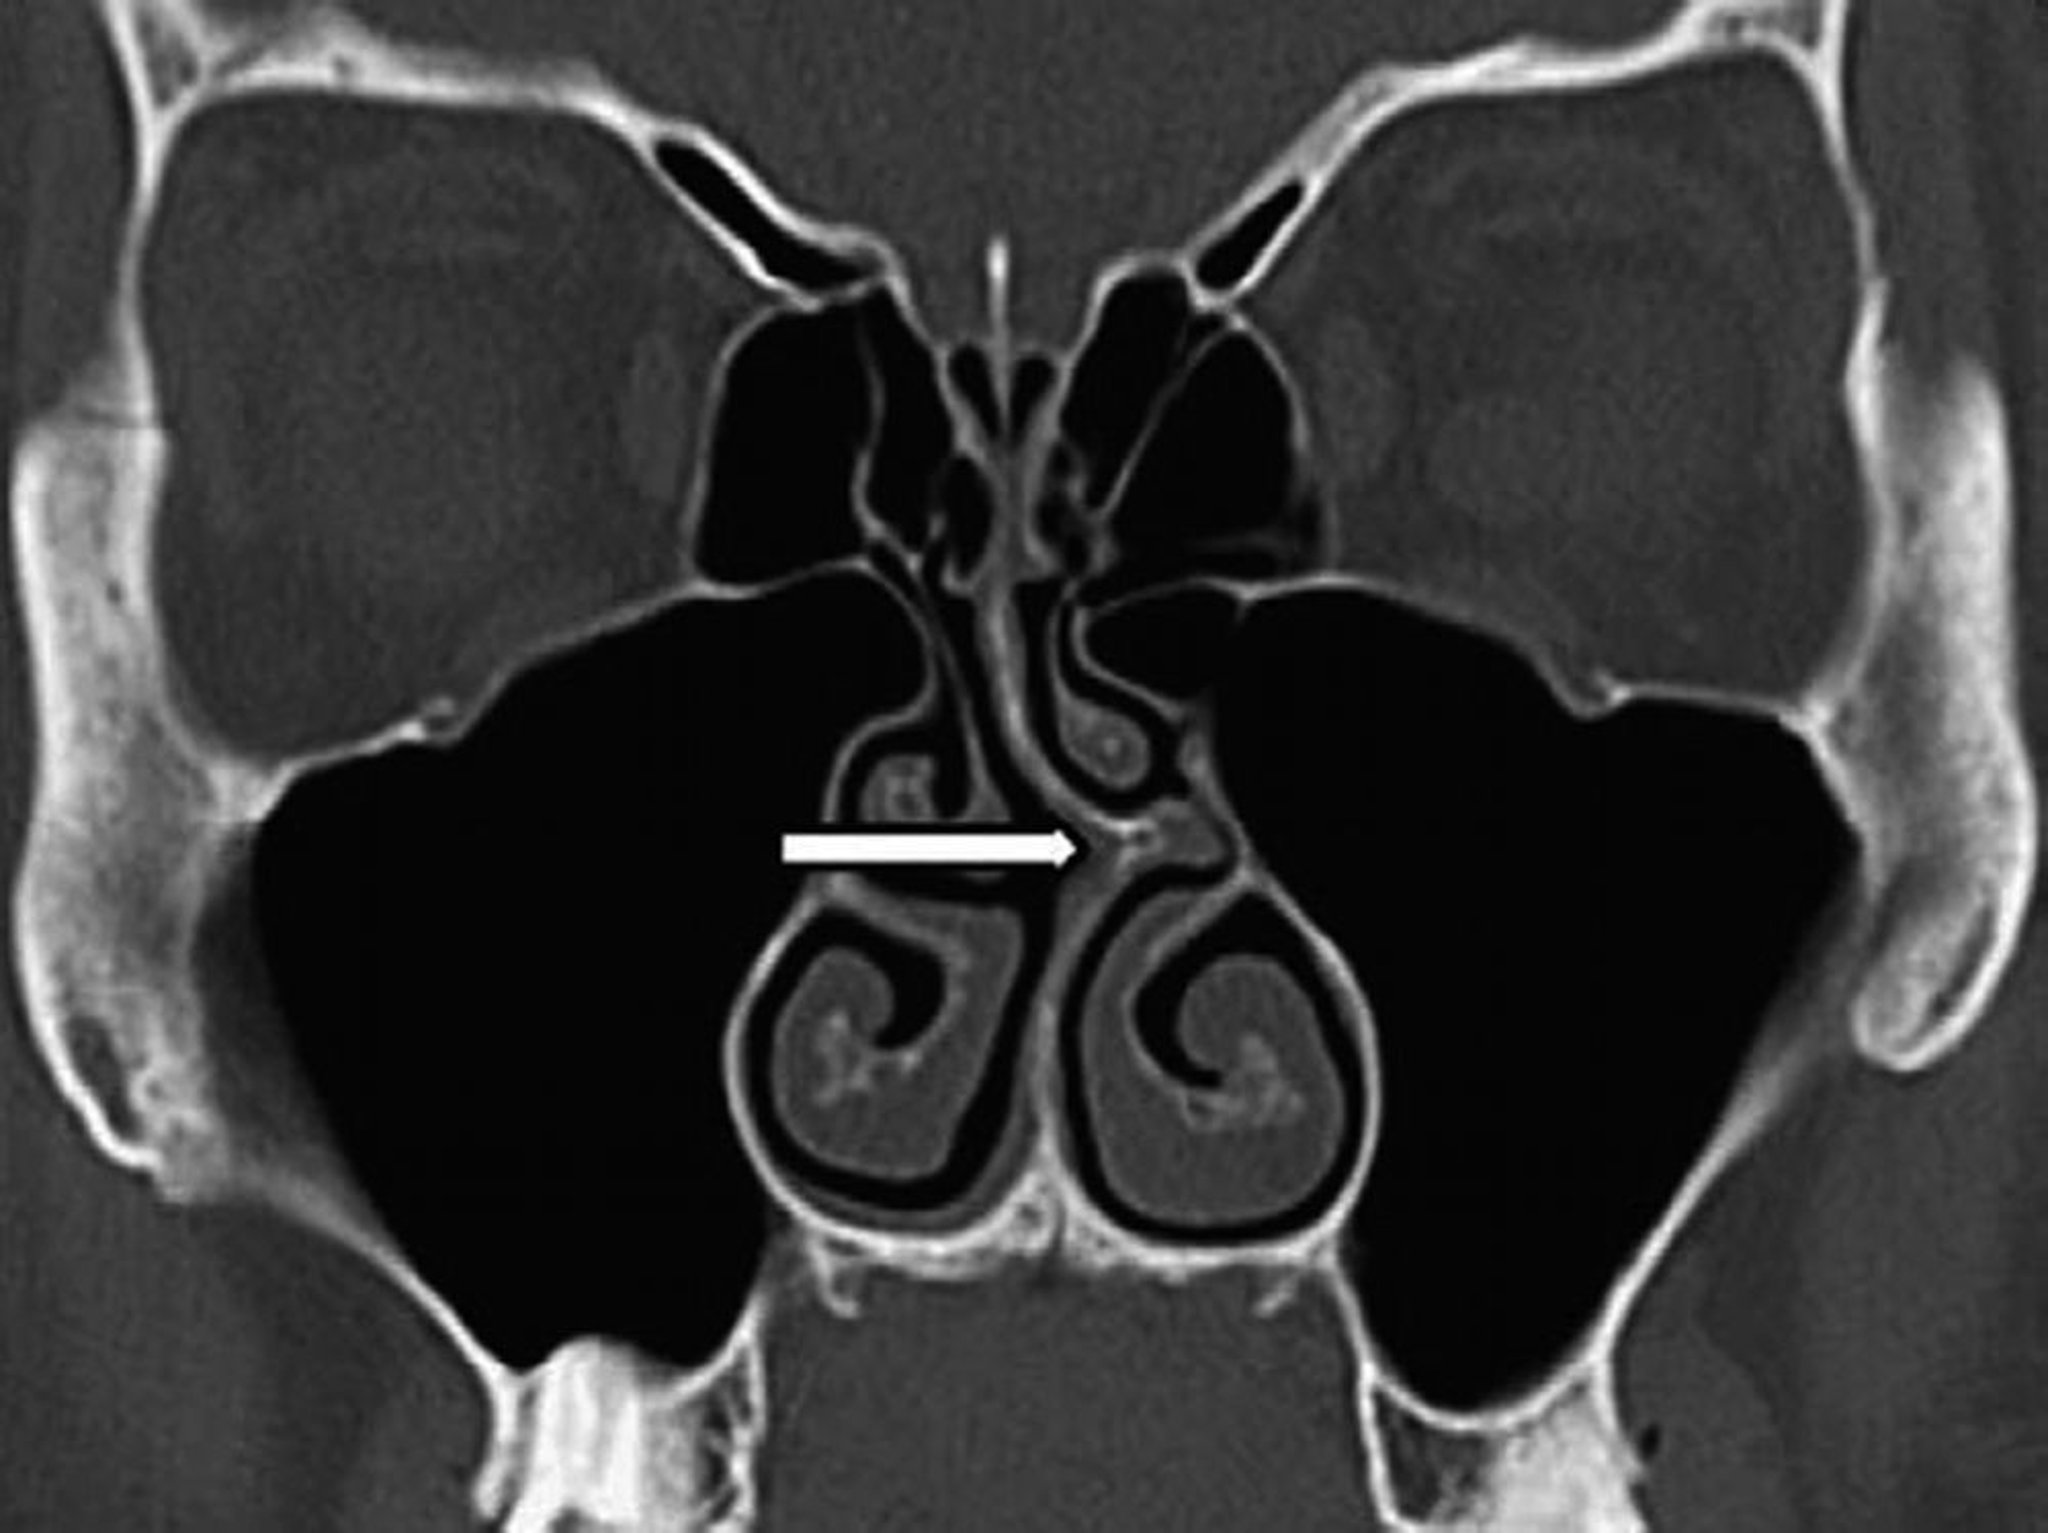

Desviación del tabique (TC)

Esta TC coronal muestra la desviación del tabique nasal hacia la izquierda (flecha).